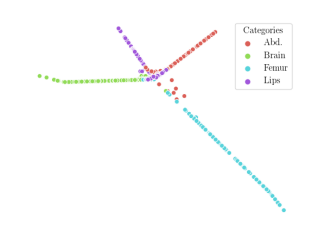

We compare the -distance of categorical features and domain features. Fig. 5 (a) shows that domain difference is higher in domain features than in categorical features. This indicates that domain features contain more domain information whereas categorical features are more domain-invariant. Fig. 6 shows the t-SNE plot of categorical features in both domains for MIDNet. From Fig. 6 (a), we observe that the categorical features learned by MIDNet enable the anatomical classification. Fig. 6 (b) shows that the learned categorical features are domain-invariant.

In addition, we utilize t-SNE plots for feature visualization in Fig. 10. Comparing Fig. 10 (a) and Fig. 10 (b), we observe that with mutual information disentanglement, (1) samples from the same category are more tightly clustered (see the top row) and (2) the source domain and the target domain are overlap more (see the bottom row). This indicates that mutual information disentanglement is important for learning categorical-focused and domain-invariant features. Fig. 10 (a), (c)-(d) show that the proposed method outperforms other state-of-the-art methods for learning category-discriminative and domain-invariant features, especially for unseen categories in the target domain (e.g., (a) vs. (d)).